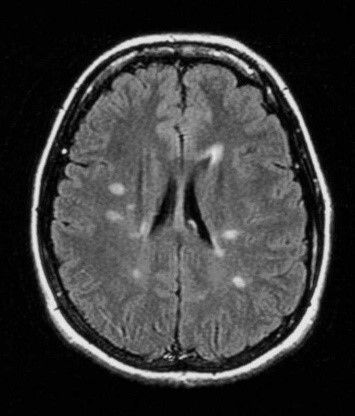

Dans le cas de la sclérose en plaques, l’IRM permet de visualiser les endroits où la myéline, substance qui entoure les neurones, a été attaquée : cela forme des plaques sur les clichés (d’où le nom de la maladie).

L’IRM permet aussi de distinguer des plaques actives qui témoignent d’une inflammation en cours. Ces plaques actives fixent le produit injecté pendant l’examen : le gadolinium.

On arrive très bien à distinguer les plaques anciennes et les plaques récentes.